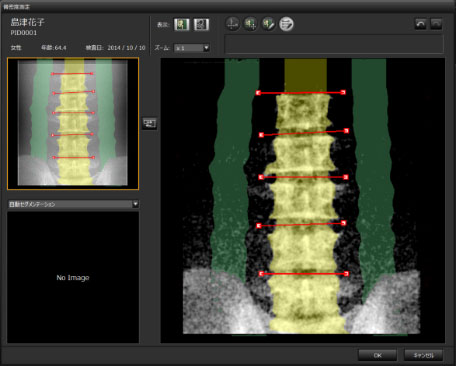

06 首发BMD功能

SONIALVISION SMIT革命性的首发BMD功能,使多功能机的工作范围进一步扩大,通过DXA法可以精准的测量病人的骨密度情况。配备拥有人工智能图像处理工作站,使骨密度检查报告更准确、快速。